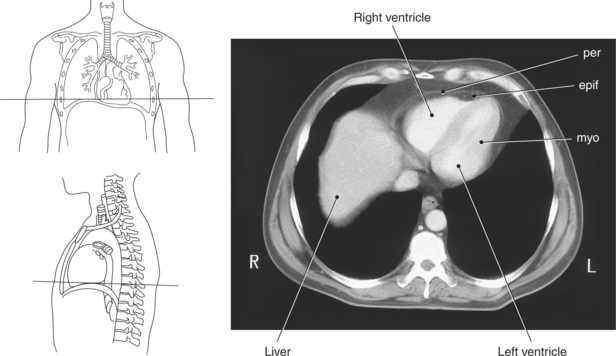

The heart is enclosed in a pericardial sac that surrounds the heart and the proximal portions of the great vessels entering and leaving the heart. The fibrous pericardium is attached to the central tendon of the diaphragm and is pierced by the inferior vena cava. The inner surface of the fibrous pericardium consists of a double-layered serous membrane termed the serous pericardium. The serous pericardial layers are the parietal layer that lines the inner surface of the fibrous pericardium and the visceral layer (epicardium) that covers the outer surface of the heart and the roots of the great vessels. Located between the two layers is a potential space (pericardial cavity) containing a thin film of serous fluid that acts as a lubricant to reduce friction to the tissues caused by heart movement. Located between the pericardium and the heart wall is a layer of epicardial fat that is typically more prominent near the venous inflow and arterial outflow of the heart (Figures 6.36 through 6.38).

The walls of the heart consist of three layers: (1) epicardium, the thin outer layer that is in contact with the pericardium; (2) myocardium, the thick middle layer consisting of strong cardiac muscle; and (3) endocardium, the thin, endothelial layer lining the inner surface. The endothelial layer also lines the valves of the heart and is continuous with the inner lining of the blood vessels. The heart is divided into four chambers: the right and left atria and the right and left ventricles. The two superior collecting chambers called atria are divided by the interatrial septum. During embryonic development an oval opening exists within the interatrial septum called the foramen ovale. This opening allows blood flow between the right and left atria during fetal lung development. At birth, the foramen ovale closes, leaving a small depression in the septal wall called the fossa ovalis in the adult heart. The two inferior pumping chambers called ventricles are divided by the interventricular septum (Figure 6.39).

The right atrium forms the right border of the heart and receives deoxygenated blood from the body via the superior and inferior venae cavae and from the coronary sinus and cardiac veins that drain the myocardium. A small muscular embryonic appendage, the right auricle, projects upward and toward the left from the right atrium, covering the root of the aorta (Figure 6.40). The right ventricle lies on the diaphragm and comprises the largest portion of the anterior surface of the heart. It receives deoxygenated blood from the right atrium and forces it into the pulmonary trunk for conveyance to the lungs. Projecting off the inferior surface of the ventricular walls are conical-shaped projections of cardiac muscle called papillary muscles that anchor the cusps of the tricuspid valve to the right ventricle (Figure 6.39). The left atrium lies posterior to the right atrium and is the most posterior surface of the heart. It also has an embryonic appendage, the left auricle, that projects to the left of the pulmonary trunk over the superior surface of the heart. The left atrium receives oxygenated blood directly from the lungs via the four pulmonary veins (two on each side). The left ventricle forms the apex, left border, and most of the inferior surface of the heart. It receives oxygenated blood from the left atrium and pumps it into the aorta for distribution throughout the systemic circuit. The myocardium of the left ventricle is normally three times thicker than that of the right ventricle, reflecting the force necessary to pump blood to the distant sites of the systemic circulation (Figures 6.41 through 6.52). Two papillary muscles project from the ventricular walls to anchor the bicuspid valve to the ventricle (Figures 6.39 and 6.47).

Figure 6.43 Axial, T1-weighted MR scan of left atrium.

Key: RV, Right ventricle; LV, left ventricle; LA, left atrium; RA, right atrium.